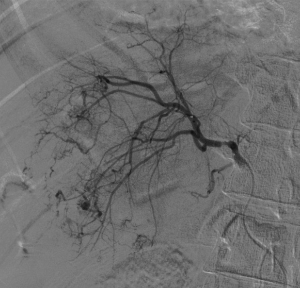

入院后,为患者给予补液,在局部麻醉下行DSA引导下经导管肝肿瘤动脉栓塞术。

肝癌破裂大出血并失血性休克患者往往病情急、危、重,如果治疗不及时可能短期内死亡。未开展介入治疗的医院对此类患者只能给予输血,补液,急诊手术,在插管全麻下行开腹手术治疗。但开腹手术往往切口长、手术时间长、手术创伤大,麻醉副作用大。可能术后出现肝功能衰竭,再出血,腹腔感染,切口疼痛,切口感染等并发症。介入手术则往往较少出现这些并发症。介入手术只需要在腹股沟穿刺一个2mm的小孔,置入导管到肝动脉,注入栓塞剂栓塞肝肿瘤的动脉,手术创伤小,止血可靠,除肝区疼痛及发热外,较少出现其它并发症,病人舒适度明显提高,而且能早期进食及下地活动,恢复快,能缩短住院时间,具有疗效好且微创的优点。